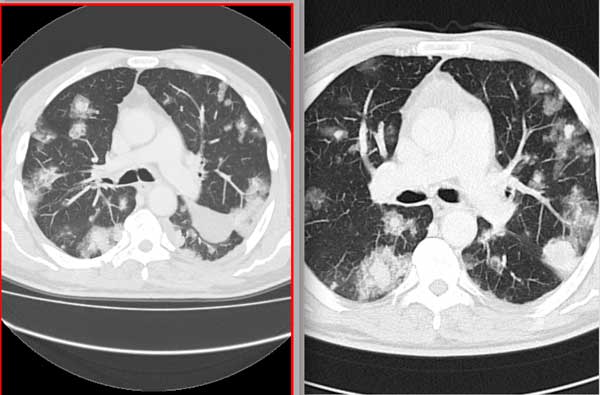

Консолидации кт

Консолидации кт 116 фотографий